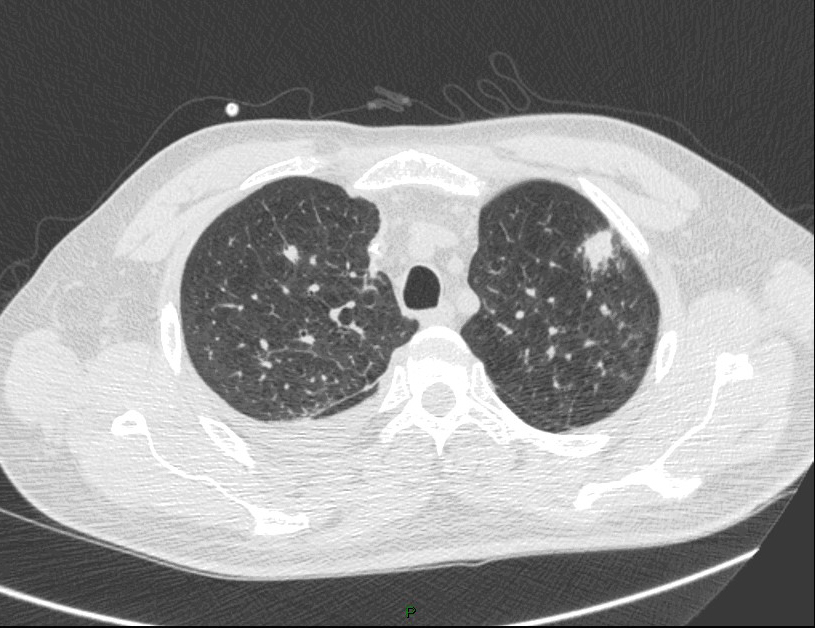

La fièvre persiste malgré les antibiotiques. Cela fait maintenant 5 jours, et vous décidez donc de réaliser un scanner thoracique dont les images sont les suivantes.

Question 13 : Comment décrivez-vous ces images ?

Nodule pulmonaire entouré de verre dépoli

Présence d’un épanchement pleural gauche

Quesyion 14 : Quelle(s) est(sont) alors les hypothèses diagnostiques devant ces images ?

Hypothèse la plus probable devant le terrain de neutropénie prolongée et les images en faveur

Absence de condensations alvéolaire ou de bronchogramme aérien

Aspergillose pulmonaire invasive = infection fongique invasive la plus fréquente chez le patient avec neutropénie prolongée (> 7 jours de neutropénie).

- imagerie :

°précoce : signe du halo : nodule unique ou multiple, avec verre dépoli autour (signe du grelot se voit dans l’aspergillome compliquant une caverne tuberculeuse par exemple) ;

°plus tardif : condensation non spécifique, puis apparition d’un croissant gazeux traduisant la nécrose du parenchyme.